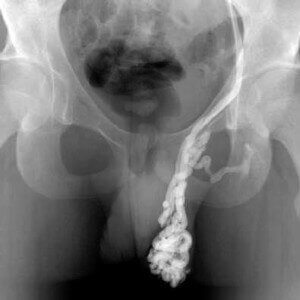

Методы диагностики

Первым делом врач проводит тщательный осмотр пациента, с пальпацией больного органа. Визуально может наблюдаться припухлость и отечность мошонки со стороны пораженного яичка, синюшный оттенок или побледнение органа.

Исследования, необходимые для точной постановки диагноза:

- пункция мошонки для микроскопического исследования экссудата;

- УЗИ мошонки;

- диафаноскопия;

- УЗДГ сосудов органа.

Клиническая картина схожа с другими патологиями, поэтому может понадобиться проведение дифференциальной диагностики, чтобы исключить или подтвердить наличие таких заболеваний как: эпидидимит, орхит, отек Квинке или гидроцеле.

На основании результатов исследования специалист ставит окончательный диагноз и подбирает наиболее адекватную тактику лечения.